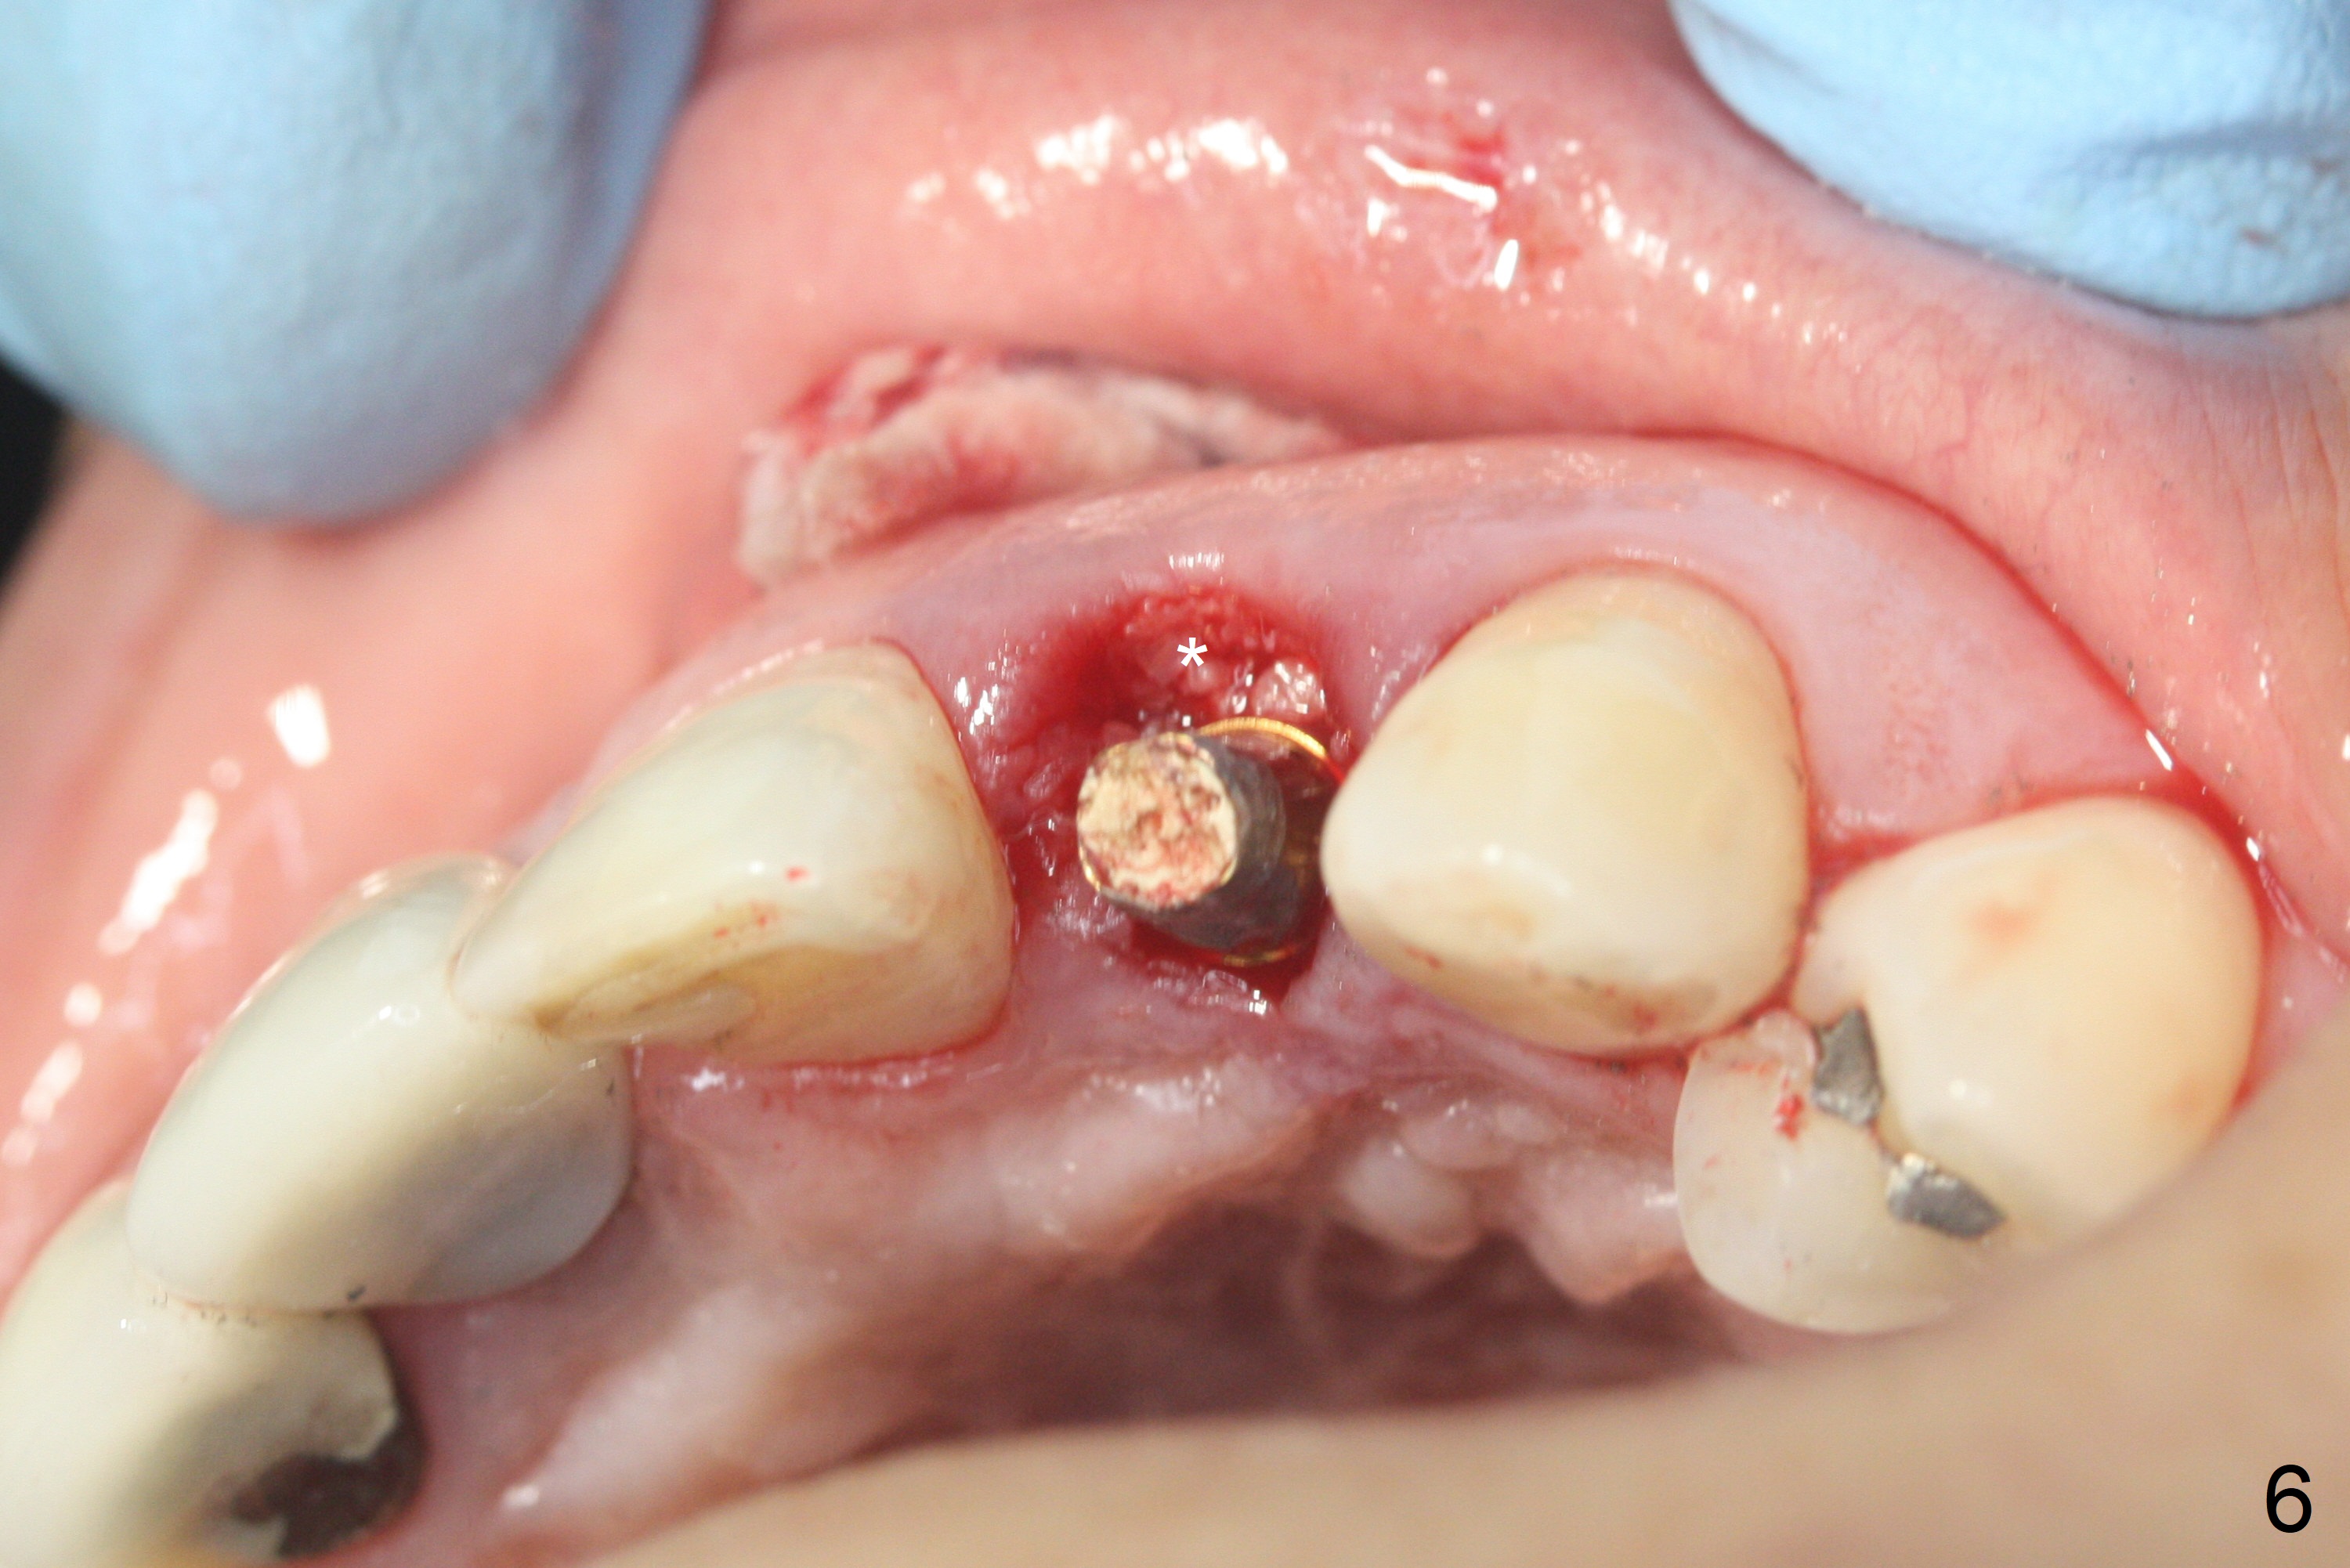

When the patient returns, the crown at #10 has displaced incisally (Fig.1,2 arrow). The initial depth is 15 mm (Fig.3, palatal gingival margin). After a 3.8x12 mm SM implant is placed (Fig.4), allograft is packed in the peri-implant space (*, as compared to Fig.3) and a 3.9x4(3) mm abutment is placed (A). More allograft is placed in the peri-abutment space (Fig.6 *). The existing crown (Fig.4,5 C) is hollowed, relined (R) and used as an immediate provisional (Fig.7-9). The patient is pleased with the appearance of the apically-repositioned provisional (Fig.7 arrow). She returns for impression 3.5 months postop (Fig.10). After change of abutment to 3.9x4(4.5) mm and new provisional, impression is retaken 5 months postop (Fig.11,12). It appears that the implant is palatally placed and a little large for the site (Fig.11 (B: buccal); Fig.12 (^: thin layer of the palatal plate)). If an angled abutment were used, a screw-retained crown might have been feasible. Due to the new provisional, the gingiva looks healthy when a permanent crown is cemented (Fig.13).